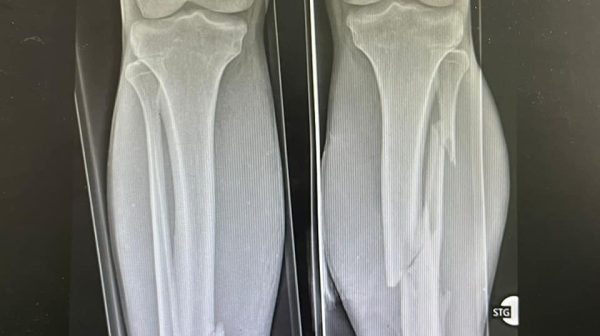

Medicii arădeni au salvat picioarele unui tânăr, victima unui accident rutier: intervenția a durat aproximativ șase ore

Intervenție de aproximativ șase ore pentru a reda mobilitatea unui tânăr de 30 de ani, victima unui accident rutier. Tânărul,  transportat de urgență, cu elicopterul SMURD, a fost examinat de medicii din UPU și diagnosticat cu fracturi la nivelul gambelor, omoplatului și bazinului. Medicii de gardă din Secția Clinică Ortopedie și Traumatologie – dr. Lehel Pal – medic primar și…